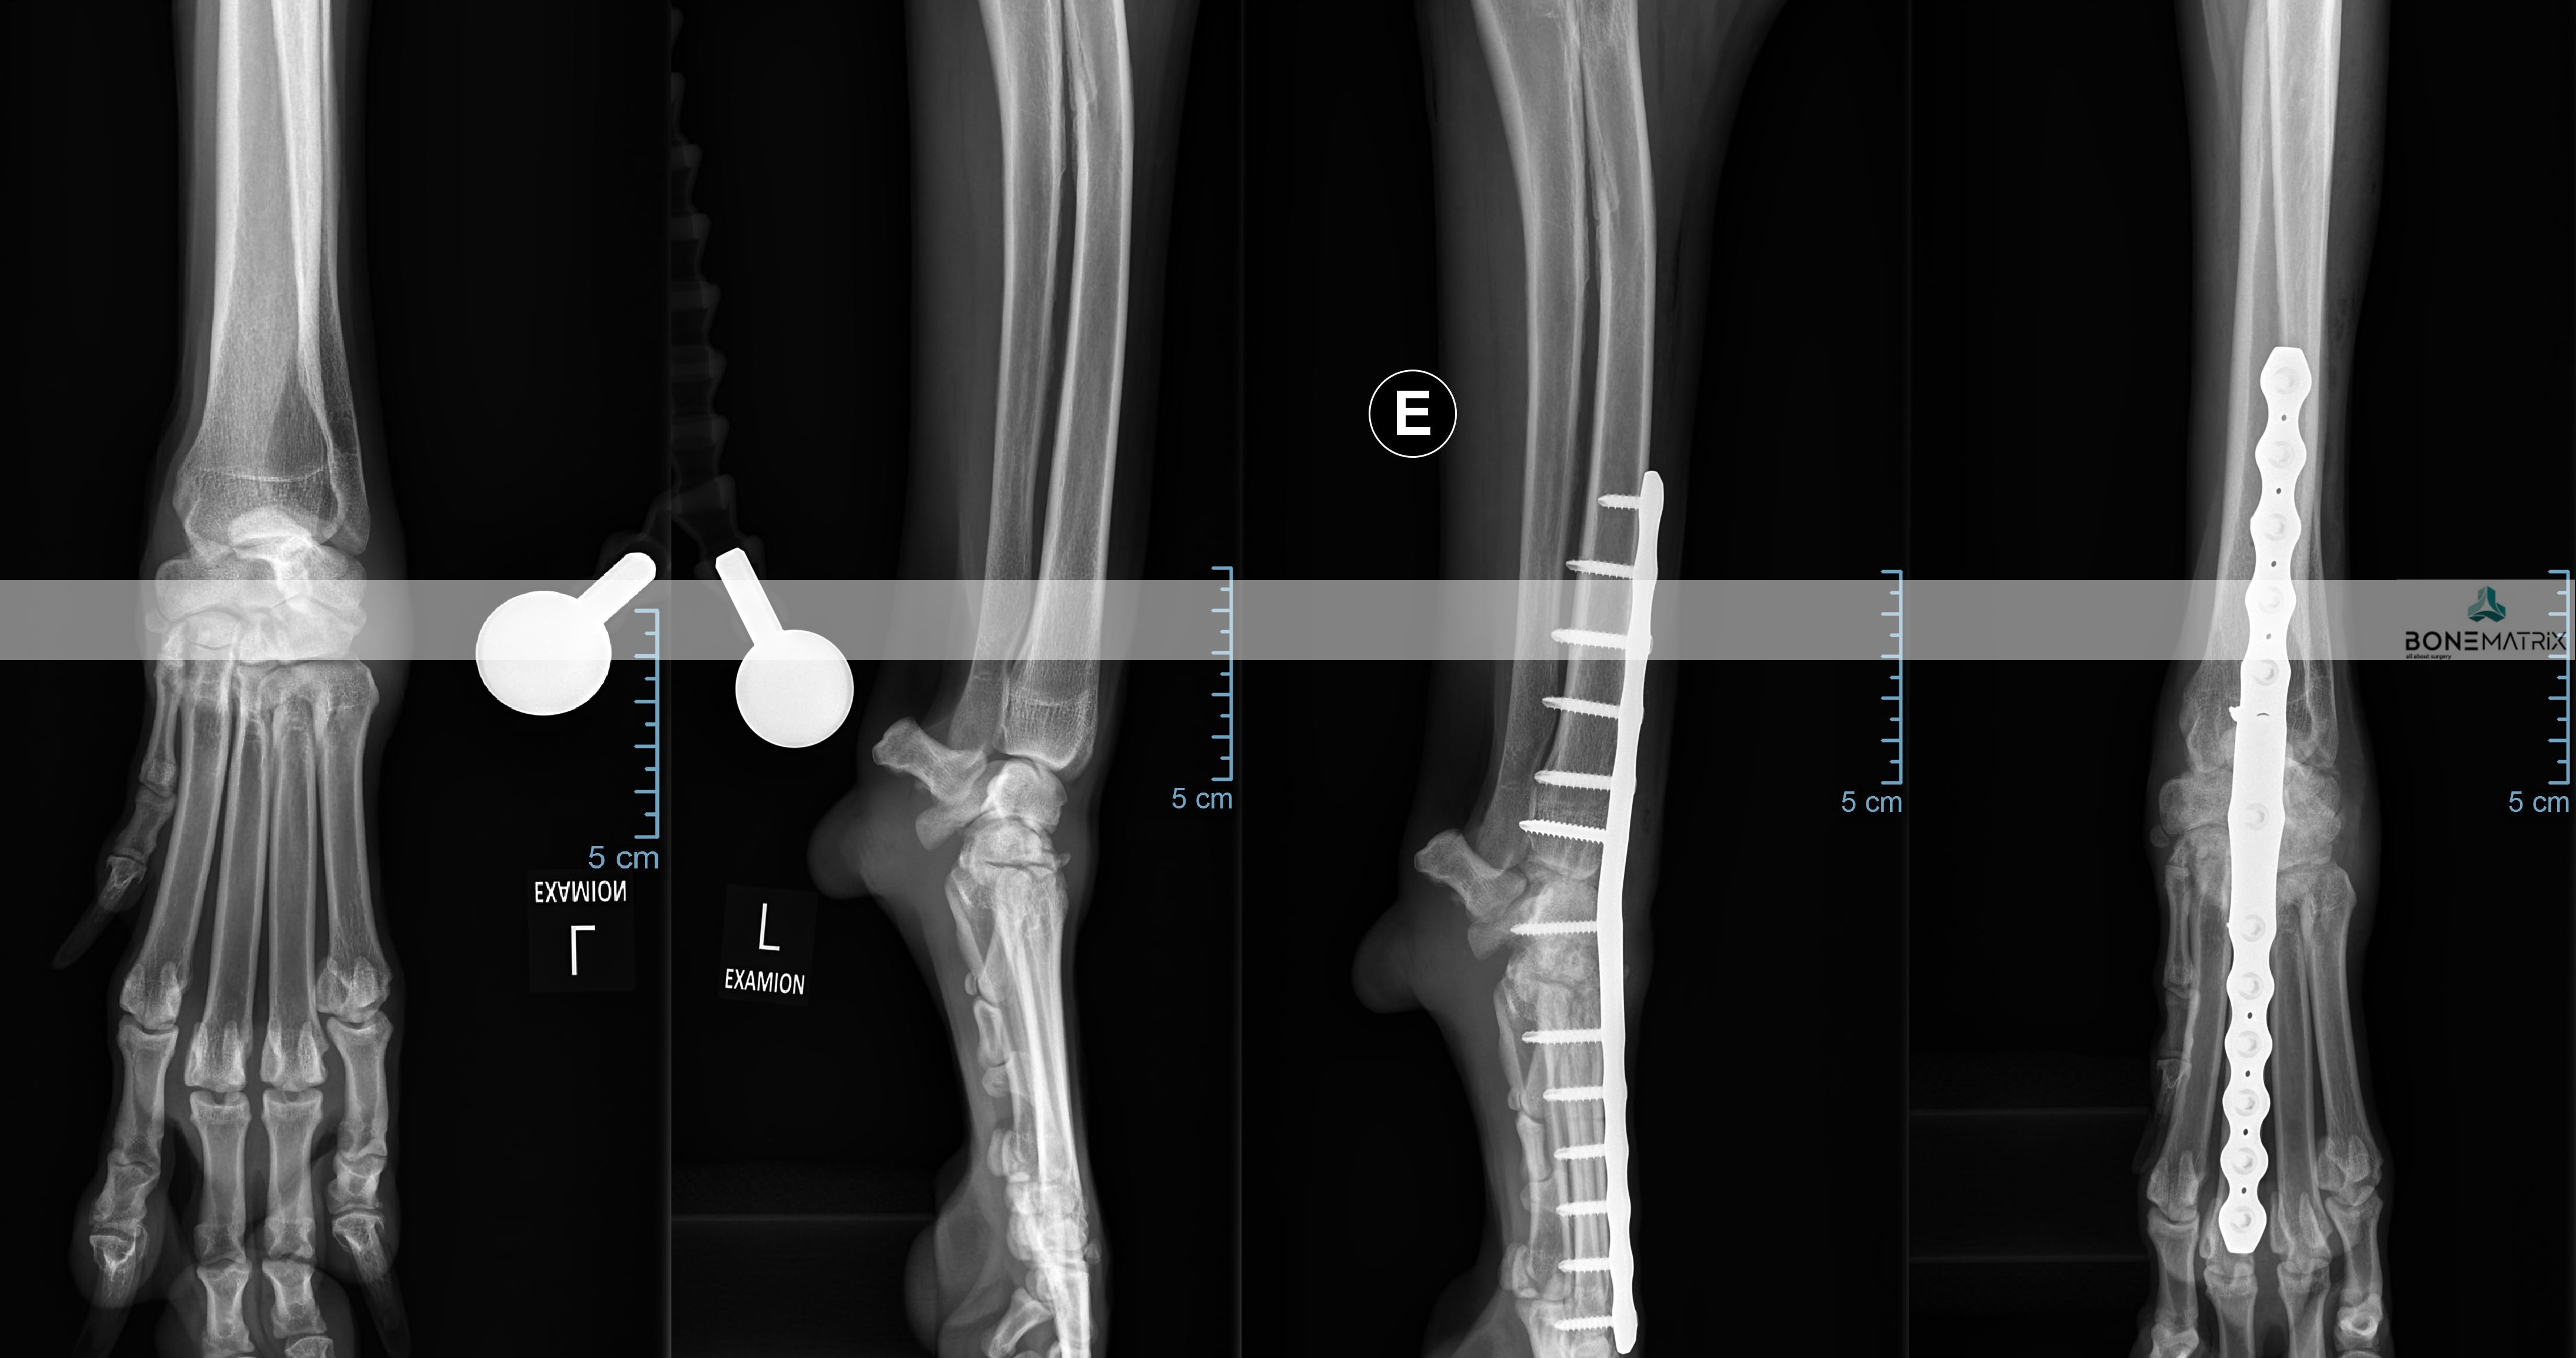

O que é?

As deformidades angulares são patologia que podem assumir as mais variadas apresentações.

A sua origem pode estar relacionada com fatores genéticos, traumas sofridos durante a imaturidade do animal, pode apresentar-se como uma doença de desenvolvimento e pode também ter influências ambientais ou nutricionais.

Todas elas se caracterizam-se por um desvio na correta forma de um determinado osso ou membro.

Que consequências podem surgir da apresentação de uma deformidade angular?

As consequências da apresentação de deformidades angulares estão em muito relacionadas com a localização destas e com a exuberância da apresentação.

Estes desvios da conformação normal podem provocar desde osteoartrite articular ou laxitude dos mecanismos de estabilização de articulações até incapacidade na realização da marcha do animal afetando severamente a qualidade de vida deste.

Como diagnosticar/ Sinais?

O diagnóstico é realizado por meio de análise clinica da anatomia dos membros e é estudada por norma através da realização de um estudo radiográfico.

O animal poderá ser desde assintomático a apresentar sintomas que passam por claudicação, lesões em estruturas articulares consequentes destes desvios angulares, incapacidade na realização de determinados movimentos até incapacidades severas de mobilidade.

A realização de um estudo radiográfico é imprescindível para definição de um planeamento cirúrgico de correção.

Em casos mais complexos pode ser necessário o recurso a estudos de imagem avançada, tanto para o estudo da deformidade como para a produção de instrumentos de cirurgia (guias de corte 3D, produção de placas com customizadas) para que seja realizada a cirurgia com precisão.

Qual o tratamento indicado?

O tratamento depende sempre da forma da patologia apresentada.

Por norma envolve realização de cortes ósseos, definidos com determinada angulação para que seja corrigida a deformidade angular, com subsequente estabilização da fratura induzida com a utilização de placas e parafusos bloqueados (sistema que oferece a maior segurança para a estabilização de fraturas).

DFO (distal femoral osteotomy) é um procedimento realizado como parte integrante ou abordagem única à patologia de luxação de patela (rótula).

A realização desta cirurgia implica a realização pré-cirúrgica de um planeamento cirúrgico baseado num estudo radiográfico.

No estudo realizado são feitas medições de vários ângulos relacionados com o alinhamento do membro posterior. Estes ângulos influenciam a direção sob a qual é exercida força sobre o joelho, podendo conduzir à luxação de patela.

Caso exista uma deformidade angular no fémur, é aconselhada a correção do ângulo em causa através da técnica DFO, para que a patela consiga permanecer alinhada na sua localização anatómica (sulco troclear).

A técnica consiste na realização de dois cortes no osso, para correção do defeito angular, e posterior estabilização dos cortes feitos com recurso a placas e parafusos bloqueados (implantes com um grau de segurança superior).

PTO (proximal tibial osteotomy) é um procedimento cirúrgico utilizado para correção de deformidades angulares presentes na tíbia.

A realização deste procedimento exige um estudo radiográfico com planeamento cirúrgico anterior ao procedimento cirúrgico. Neste são medidos ângulos relacionados com o alinhamento do membro posterior.

A cirurgia consiste na realização de dois cortes, previamente planeados, na tíbia, seguindo-se a sua estabilização por meio de placa e parafusos bloqueados (estes implantes apresentam um alto grau de segurança na sua utilização).

Dada a versatilidade desta técnica, várias patologias podem ser corrigidas com esta abordagem, nomeadamente luxações de patela e outras deformidades do membro posterior.

Nesta cirurgia também são utilizadas com frequência guias 3D que definem o local de corte com elevada precisão. Estas guias são planeadas a partir de imagem de TAC em softwares de especialidade e seguidamente são produzidas no nosso laboratório 3D, de forma a estarem adaptadas as características individuais de cada paciente.